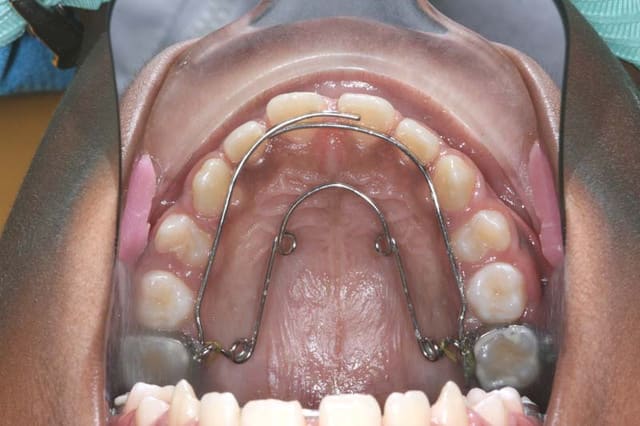

je tente donc un Q.H. Crozat, sans rien d’autre

à suivre